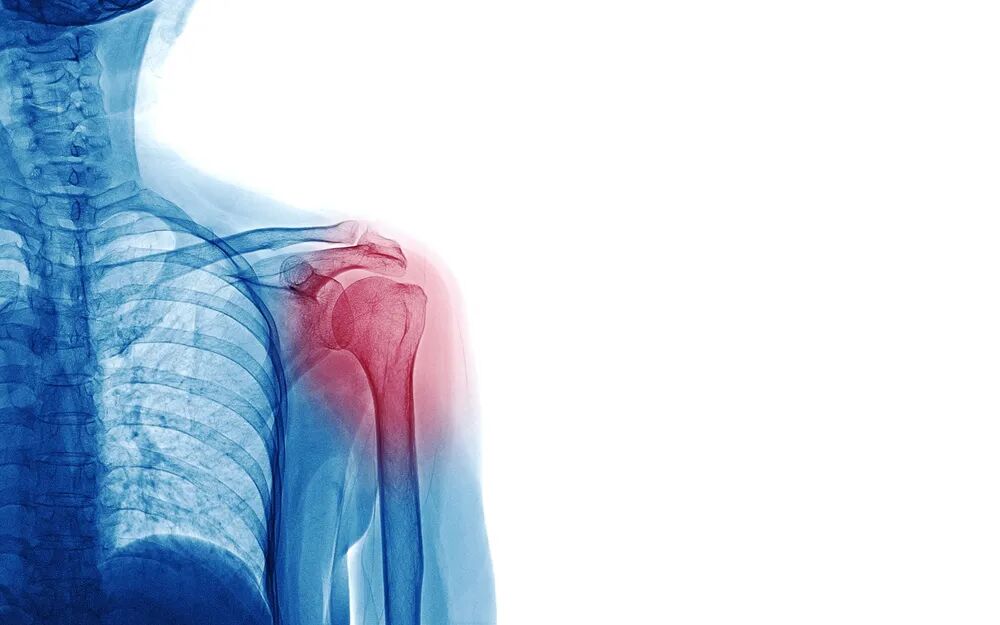

“五十肩”会引起肩膀痛。究其原因,不外乎长期工作劳动导致肩部肌肉、关节、韧带发生慢性劳损,如果每次劳动后都不能得到很好的休息、放松,久而久之,肩膀就会出现疼痛不适。因为好发于五十岁上下的中年人,因此被称为“五十肩”,而且患者往往肩膀不能外展、上举、后伸上臂,甚至连梳头、洗脸、叉腰的动作都做不了,一做就痛,肩膀就像被卡住、冻住一样,又称之为“冻结肩”。